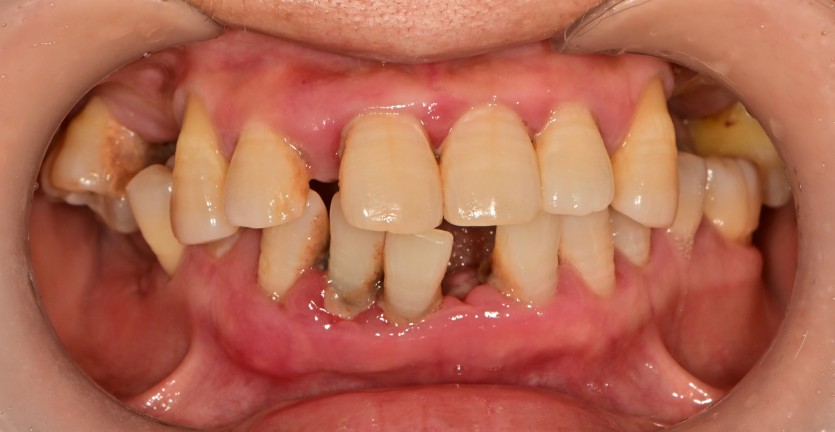

전체 임플란트 증례입니다.

18개의 임플란트로 완성하였습니다.